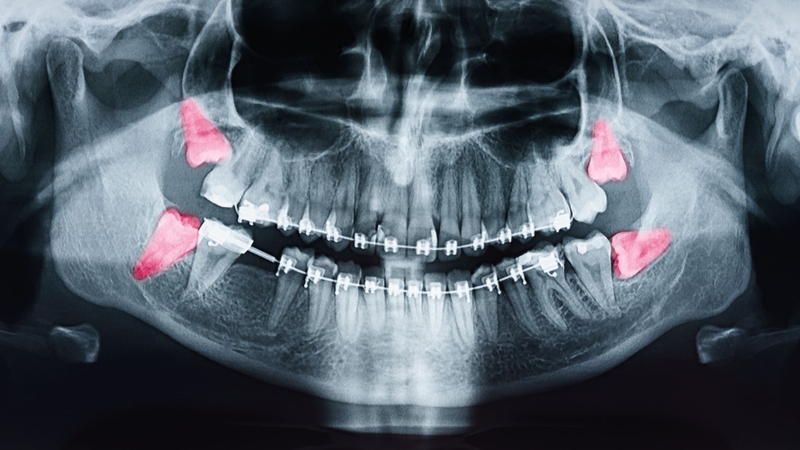

Răng khôn còn được gọi là răng số 8 hoặc răng hàm lớn thứ ba, thường bắt đầu mọc vào khoảng độ tuổi từ 17 - 25. Thông thường, nếu răng khôn mọc bình thường, chúng sẽ không hại cho sức khỏe răng miệng. Tuy nhiên, trong một số trường hợp, khi khoang miệng hẹp hoặc không có đủ không gian, răng khôn có thể mọc kẹt một phần hoặc hoàn toàn trong xương.

Nếu bạn đã đủ 32 chiếc răng, bạn sẽ có 4 răng khôn, trong đó có 2 răng khôn ở hàm trên và 2 răng khôn ở hàm dưới. Khi răng khôn mọc không đúng hướng, kẹt trong xương, có thể gây đau đớn, nhiễm trùng hoặc sâu răng.